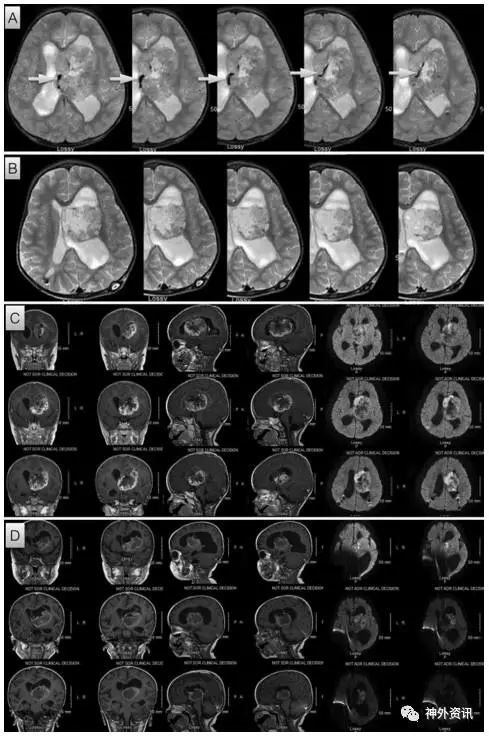

图1. MRI成像显示左脑室内肿瘤在辅助化疗前、后供应血管和肿瘤体积的变化。A.辅助化疗前肿瘤内侧有一较粗的供应血管(箭头所指);B.辅助化疗后该血管消失,并且肿瘤信号发生改变;C、D.辅助化疗前与辅助化疗后的MRI成像提示,瘤体缩小35%,强化明显减弱。